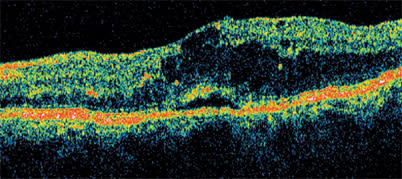

The difference between drusen and CNV is clearly delineated with the Stratus OCT. Therefore, for the general ophthalmologist, it is a useful tool for deciding when to refer for treatment a patient whose dry AMD has progressed to neovascular disease.

In this patient with a pigment epithelial detachment and cystic changes, FA showed a minimally classic retinal angiomatous proliferation lesion. OCT confirmed that re-treatment was not necessary.